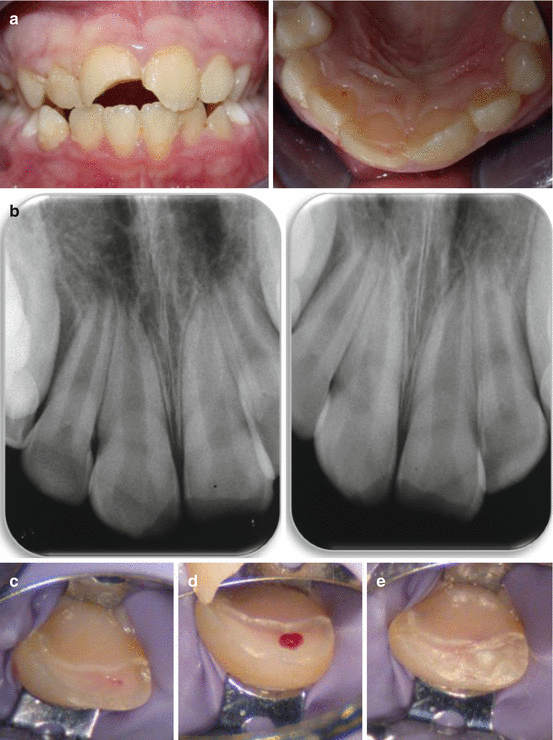

From pocketdentistry.com

Pulpal treatment in young permanent incisors following traumatic Glass Ionomer Pulpotomy Acceptable materials for restoration of carious primary molars, with good supporting evidence, are: Accordingly, the restoration materials reported by the included studies were different (composite, amalgam, glass ionomer. Glass Ionomer Pulpotomy.

From www.researchgate.net

Procedure sequence. (A) Absolute isolation of the operative field with Glass Ionomer Pulpotomy Acceptable materials for restoration of carious primary molars, with good supporting evidence, are: Accordingly, the restoration materials reported by the included studies were different (composite, amalgam, glass ionomer. Glass Ionomer Pulpotomy.